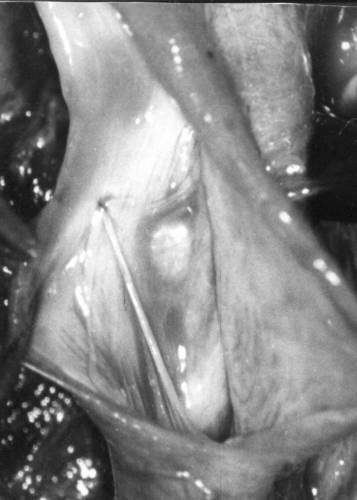

Результат микрохирургической реконструкции несостоятельного венозного клапана.